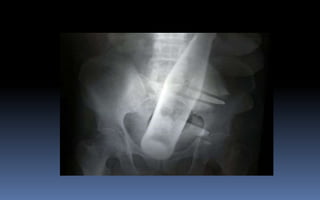

PROYECCION SIMPLE DE ABDOMEN

CRITERIOS DE EVALUACION P.S.A.

 Apreciar desde el abdomen

superior hasta la sínfisis del

pubis.

 Lumbares, pelvis y ultimas

costillas sin rotación.

 Apófisis espinosas en el

centro de cuerpos

vertebrales.

 Ver el bazo, riñones, psoas

y “borde inferior hepático

INTERPRETACION

 Estructuras óseas

(densidades).

 Tejidos blandos.

 Psoas.

 Bazo.

 Niveles Hidroareos.

 Intestino delgado.

 Colon.

 Silueta Renal.

PATRON AEREO DEL INTESTINO

COLELITIASISNEFROMEGALIA

ILEO FUNCIONALVOLVULO DEL SIGMOIDES

OBSTRUCCION DE ILEON

NEUMOPERITONEO

SIGNO DE LA DOBLE

PARED

ASCITIS

HEMOPERITONEO